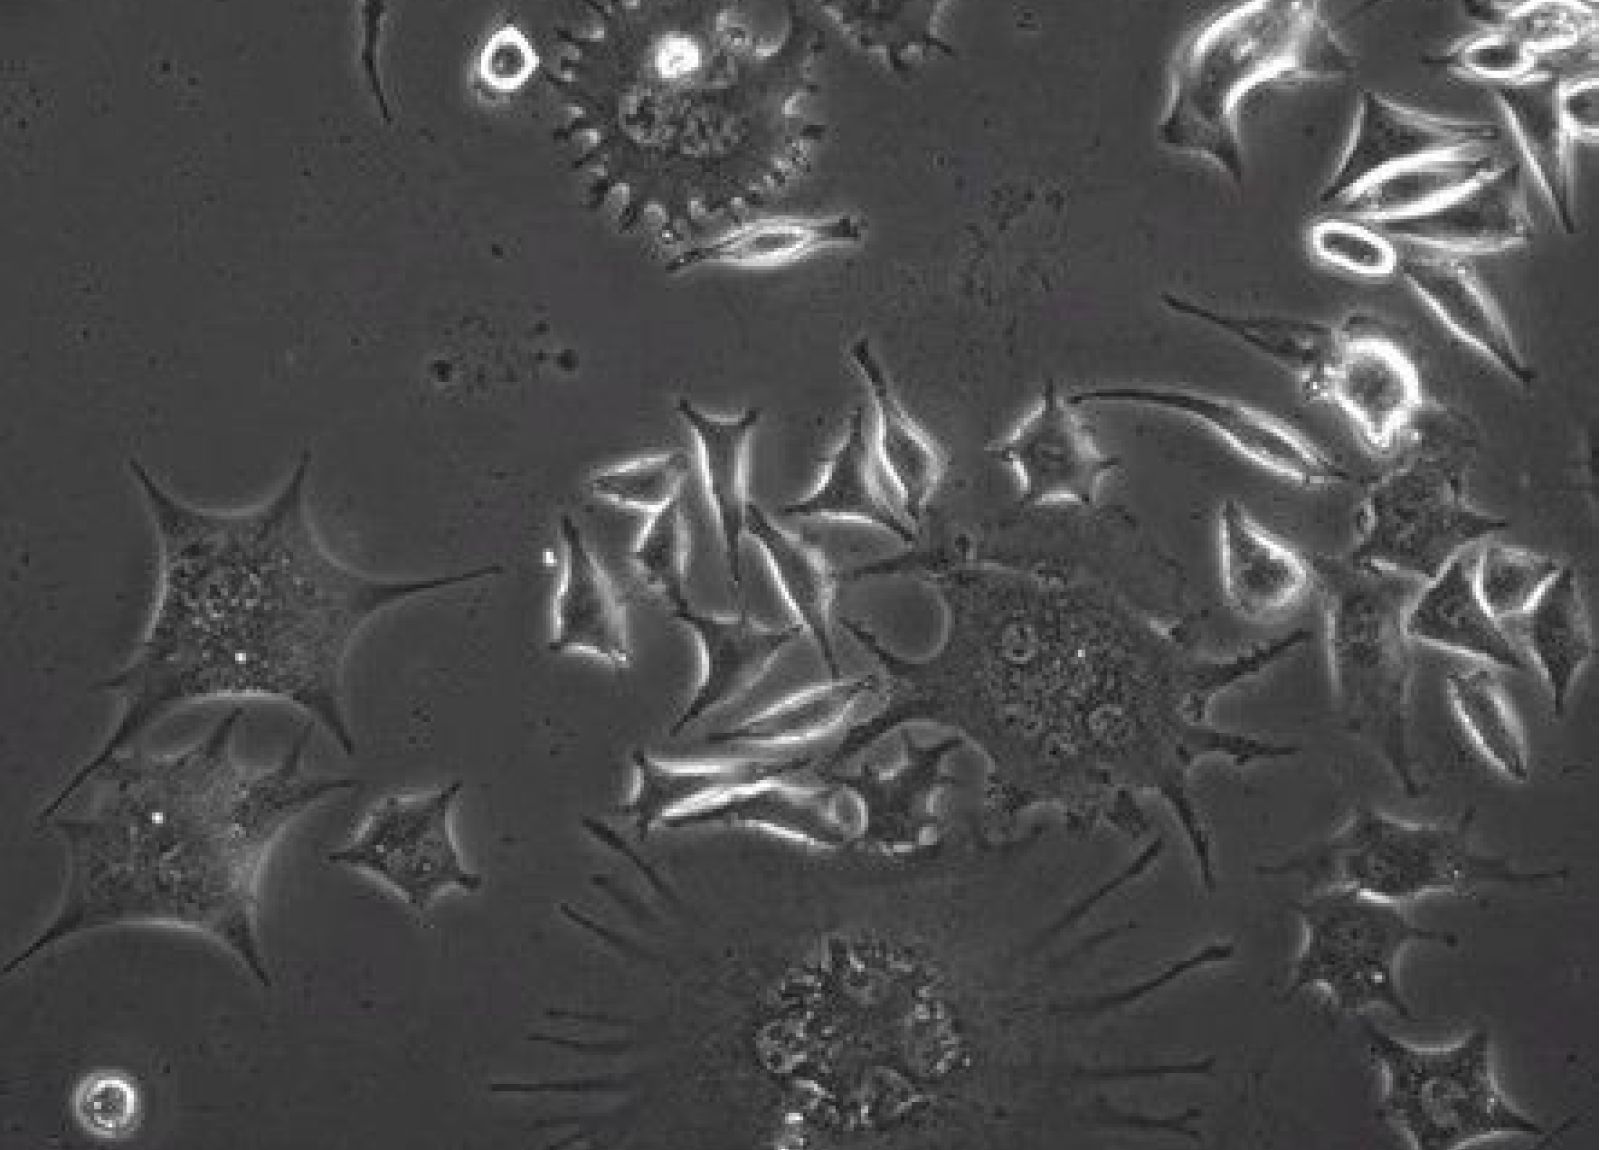

Automatická detekce živých buněk

Vyvíjíme metody pro automatizovanou analýzu buněk z mikrokinematografických záznamů pomocí konvolučních neuronových sítí (CNN). Optimalizovaný model CNN umožňuje detailní analýzu interakcí buněk se vzorkem, což je klíčové pro další fáze výzkumu.

Na obrázku: Automaticky detekované buňky pomocí natrénovaného modelu CNN

Testování cytotoxicity kapalných vzorků

Pomocí pokročilé obrazové analýzy živých buněk testujeme cytotoxicitu kapalných vzorků, včetně výluhů a extraktů z pevných látek. Využíváme časosběrnou mikrokinematografii, která umožňuje dlouhodobé sledování buněčných reakcí bez barvení, čímž odhalujeme i jemné morfologické a růstové změny.

Na obrázku: Odhalené buněčné anomálie

Testování biokompatibility pevných vzorků

Testujeme biokompatibilitu pevných vzorků sledováním interakcí živých buněk s povrchem materiálů. Pomocí časosběrné mikrokinematografie analyzujeme růst, přilnavost a chování buněk v kontaktu se zkoumaným materiálem, což umožňuje posoudit jeho vhodnost pro biomedicínské aplikace.

Na obrázku: Interakce živých buněk s povrchem implantologické materiálu na bázi titanu